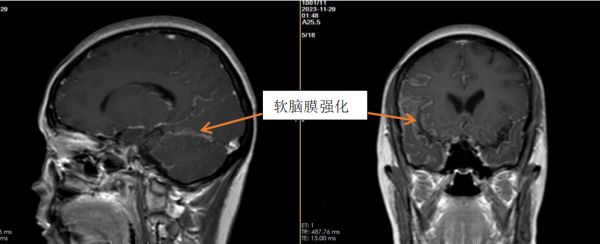

我院神经内二科杜浩勇医生接诊了患者。经详细追问病史,了解到患者既往体健。查体未见明显阳性体征。MR颅脑平扫+增强显示患者颅内软脑膜及所示颈髓软脊膜广泛异常强化,不排除颅内感染、脑膜转移可能(见图一),遂给予患者行肿瘤标志物检查。结果提示癌胚抗原34.70ng/ml,高;糖类抗原199:32.50U/mL,高;糖类抗原125:44.20U/mL,高;糖类抗原153:27.80U/mL,高。患者肺部CT提示右肺上叶尖段占位,考虑周围型肺癌;食管中下段稍扩张,胃底壁可疑增厚(见图二)。腰椎穿刺显示:白细胞计数35×106/L,高;脑脊液蛋白(CSFP)1.24g/L,高;细胞学呈淋巴-单核细胞反应型,以淋巴细胞为主,可见异形细胞,考虑肿瘤细胞可能性大。

图二:1.右肺上叶尖段占位,考虑周围型肺癌;2.食管中下段稍扩张,胃底壁可疑增厚。